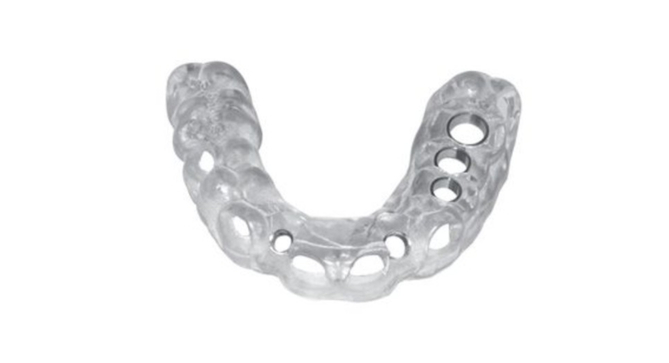

Thông thường, sau khi lập kế hoạch phẫu thuật cấy ghép như hình dưới đây,

một lỗ sẽ được khoan tại vị trí đặt và một hướng dẫn phẫu thuật kỹ thuật số được thiết kế cùng nhau.

(Lỗ là nơi cấy ghép implant)

Thiết kế hướng dẫn phẫu thuật kỹ thuật số

Hướng dẫn phẫu thuật kỹ thuật số được thiết kế

trên máy tính sẽ được in ngay lập tức bằng thiết bị in 3D.

Hướng dẫn phẫu thuật in 3d (Nguồn: Image3dconversion)

Hướng dẫn phẫu thuật kỹ thuật số cuối cùng được sử dụng

sau khi in và trải qua quá trình xử lý bổ sung trông như sau.

Tại vị trí đặt implant đã được khoan một lỗ nên tất cả

những gì bạn phải làm là đặt implant theo đúng lỗ.

Hướng dẫn phẫu thuật kỹ thuật số Implant